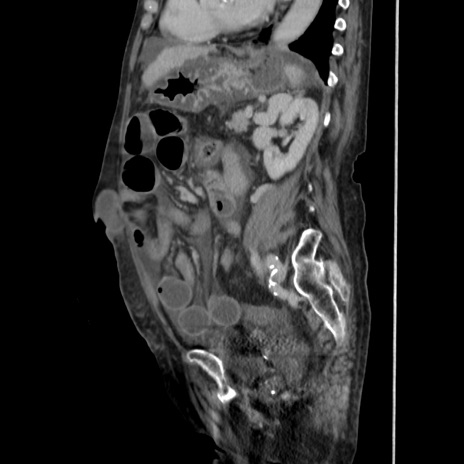

横断像

【症例】80歳代 女性

【主訴】腹部膨満感

【現病歴】他院にて肝硬変にてフォロー中。1週間前から便秘、腹部膨満感、臍部腫瘤あり受診となる。

【既往歴】肝硬変

【身体所見】腹部膨隆あり、皮膚変化なし、疼痛なし。

【データ】WBC 4600、CRP 0.25